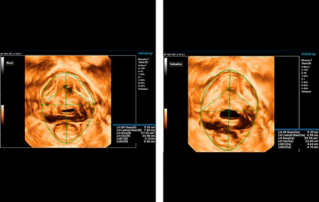

![detection-of-latent-urinary-incontinence-in-women-before-scgp.thumb.319.319 Ultrasound Journal 9 - ?? ??? ??(genital prolapse) ?? ? ??? ?? ??? ??]() Ultrasound Journal 9 - ?? ??? ??(genital prolapse) ?? ? ??? ?? ??? ??All women with genital prolapse before surgical treatment are shown additional examination to detect latent urinary incontinence. The generally accepted tactic allows you to do this examination using the invasive method of CUDI (complex urodynamic examination), a trial test with a pessary (it takes about 7 days to wear a pessary for a long time). Ultrasound of the pelvic floor with 3D reconstruction and functional tests has a significant advantage, because it is a dynamic non-invasive method of examination, which significantly accelerates and clarifies the method of surgical treatment of the patient.??? ?? | ??? ??? | ??? | OB GYN 2022-12-02

Ultrasound Journal 9 - ?? ??? ??(genital prolapse) ?? ? ??? ?? ??? ??All women with genital prolapse before surgical treatment are shown additional examination to detect latent urinary incontinence. The generally accepted tactic allows you to do this examination using the invasive method of CUDI (complex urodynamic examination), a trial test with a pessary (it takes about 7 days to wear a pessary for a long time). Ultrasound of the pelvic floor with 3D reconstruction and functional tests has a significant advantage, because it is a dynamic non-invasive method of examination, which significantly accelerates and clarifies the method of surgical treatment of the patient.??? ?? | ??? ??? | ??? | OB GYN 2022-12-02 -